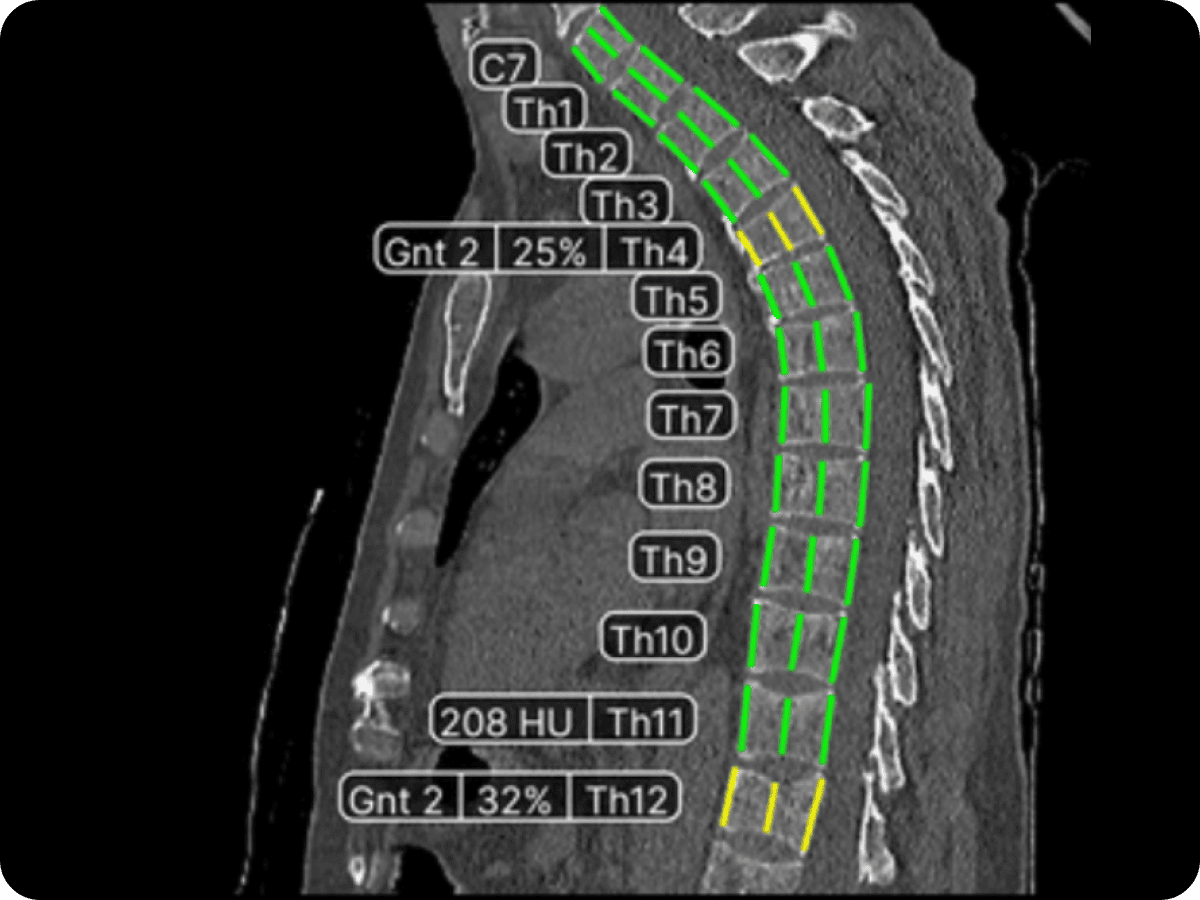

Гастроэнтерология – это сложная область медицины‚ требующая высокой квалификации врачей и доступа к современным методам диагностики․ КТ является одним из ключевых инструментов‚ позволяющих визуализировать органы брюшной полости и выявлять различные патологии․ Однако‚ анализ КТ – это трудоемкий и времязатратный процесс‚ требующий от врача внимательности и опыта․

И вот тут на сцену выходит ИИ․ Он способен автоматизировать рутинные задачи‚ такие как поиск и идентификация опухолей‚ воспалительных процессов и других аномалий․ Это позволяет врачам сосредоточиться на более сложных аспектах диагностики и лечения‚ а также сокращает время ожидания результатов для пациентов․

В основе работы ИИ лежат сложные алгоритмы машинного обучения‚ которые обучаются на больших массивах данных‚ включающих тысячи КТ-изображений с различными патологиями․ Эти алгоритмы способны выявлять закономерности и признаки‚ которые могут быть незаметны для человеческого глаза․

- Анализ изображений с использованием алгоритмов машинного обучения․

- Выделение областей‚ представляющих интерес для врача (например‚ опухоли‚ воспаления)․

- Формирование отчета с результатами анализа‚ включающего визуализацию выявленных аномалий и их характеристик․